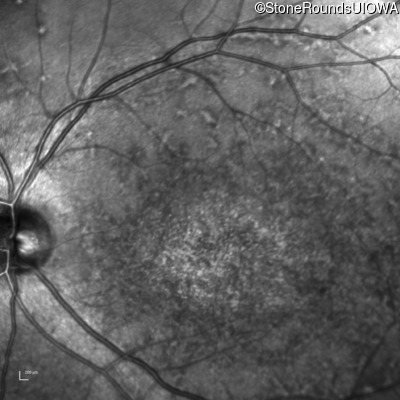

Infrared Fundus Photograph - Right - 20/200

Exemplar